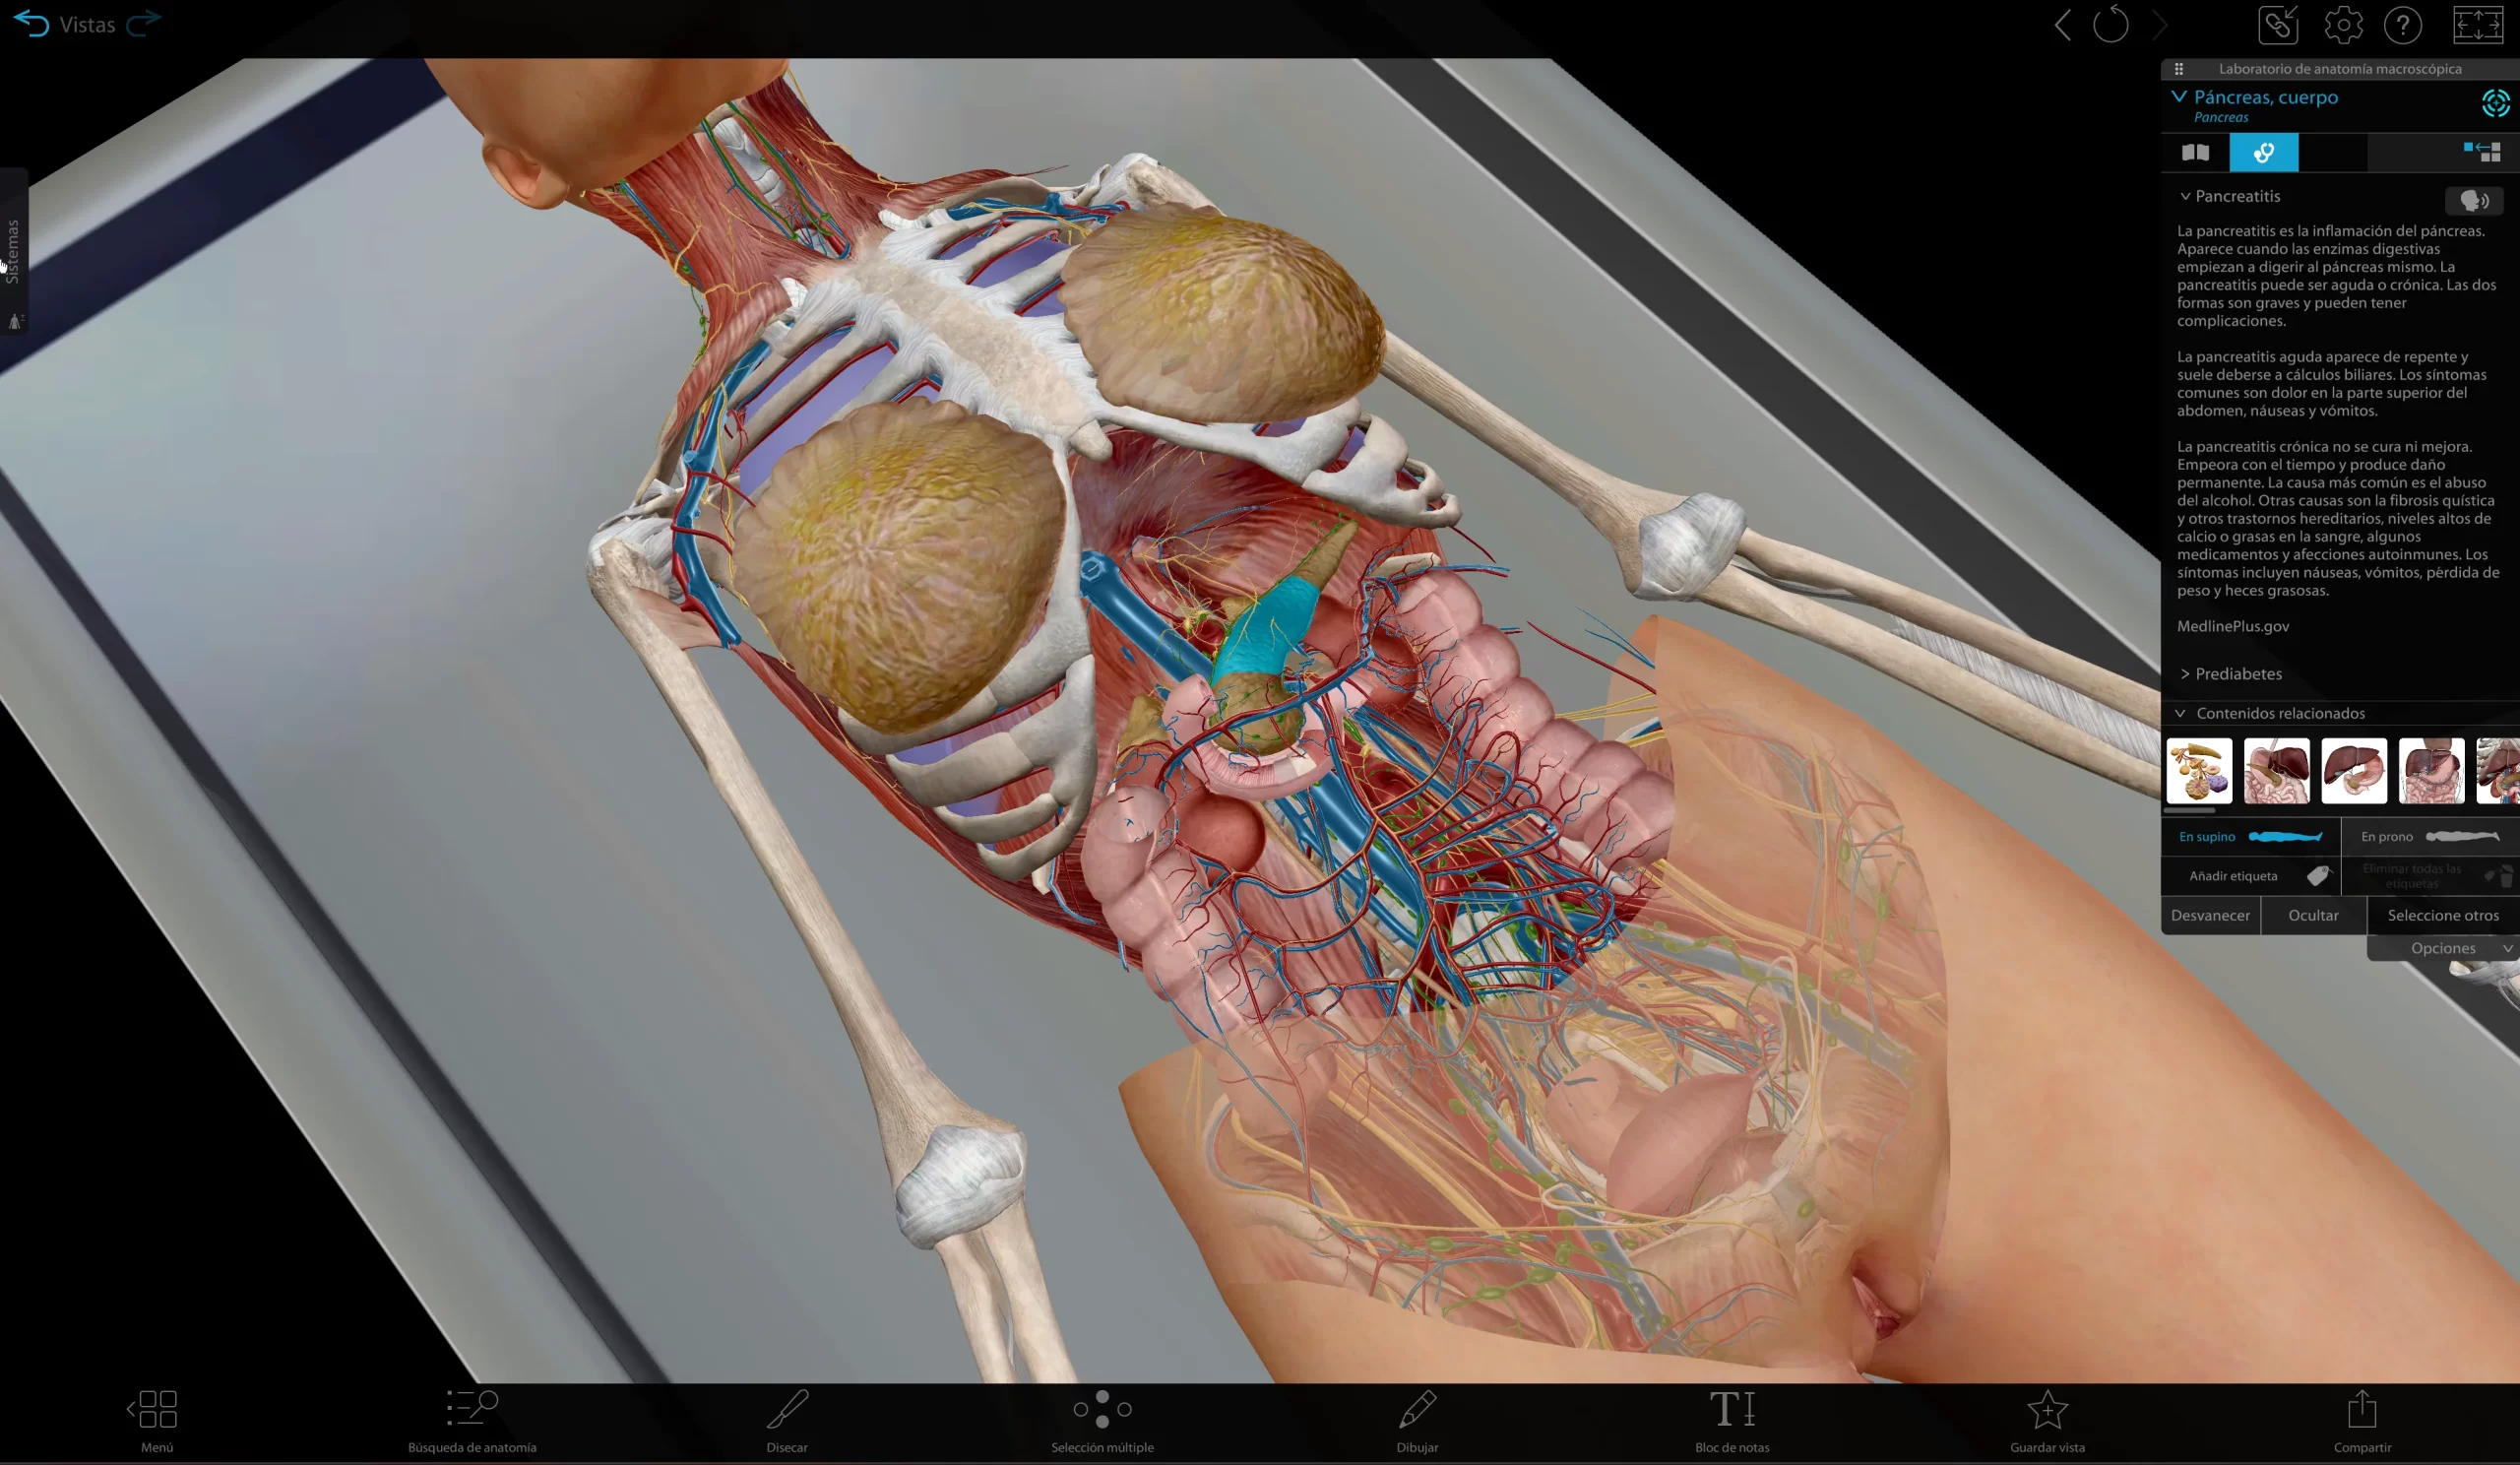

SIT Anatomy

La mesa SIT Anatomy es una solución versátil de alta tecnología con modelos 3D basados en cadáveres reales y renderizados foto realísticamente. Ofrece:

Exploración detallada de la anatomía humana y veterinaria

Herramientas interactivas de disección virtual

Visualización de imágenes DICOM y PACS

Estudio morfofuncional con correlación clínica

Ideal para facultades de Medicina, Enfermería, Fisioterapia, Veterinaria y Odontología.